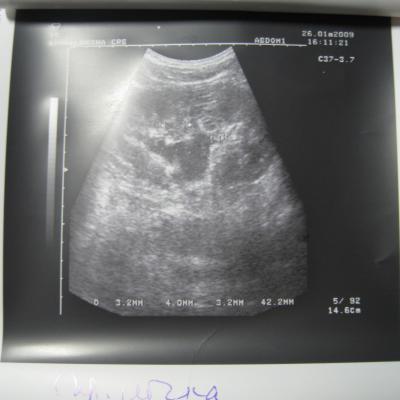

Доктор здраствуйте! мне 23 годаОколо полугода назад лежал на обследовнии в нефрологии,где был посиавлен диагноз:хр,пиелонефрит обеих почек,МКБ,микролиты обеих почек 2-4мм,наиболее крупный справа 4 мм!Было рекомендовано:курсам пить пролит,цистон,урологические сборы и тд!Все ето я принимал,почки особо не беспокоили если тока изредка небольши тупые боли в пояснице по утрам и все!Вчера решил сделать узи почек:диагноз был поставлен следующий:гидронефроз правой почки 1 степени,(врач сказал что лоханка в правой почке увеличена до 40 мм из за МКБ,лоханка левой почки 18 мм,остальные параметры в норме)микролиты обеих почек 2-4 мм,хр,пиелонефрит обеих почек особых жалоб у меня нету на данный момент!количество мочи в течении дня нормальное,удалось сдать анализы мочи(общий и по Нечипаренко.В общем анализе обнаружили немного белка,если нужны цифры могу написать завтра,но сказали что не очень много)по Нечипаренко все в норме!Более полное обследование чем узи нет возможности сделать!уролог прописал пить цистон ,уролесан и сборы трав пить и все!посоветуйте что нужно и можно делать в моей ситуации!снимок узи: